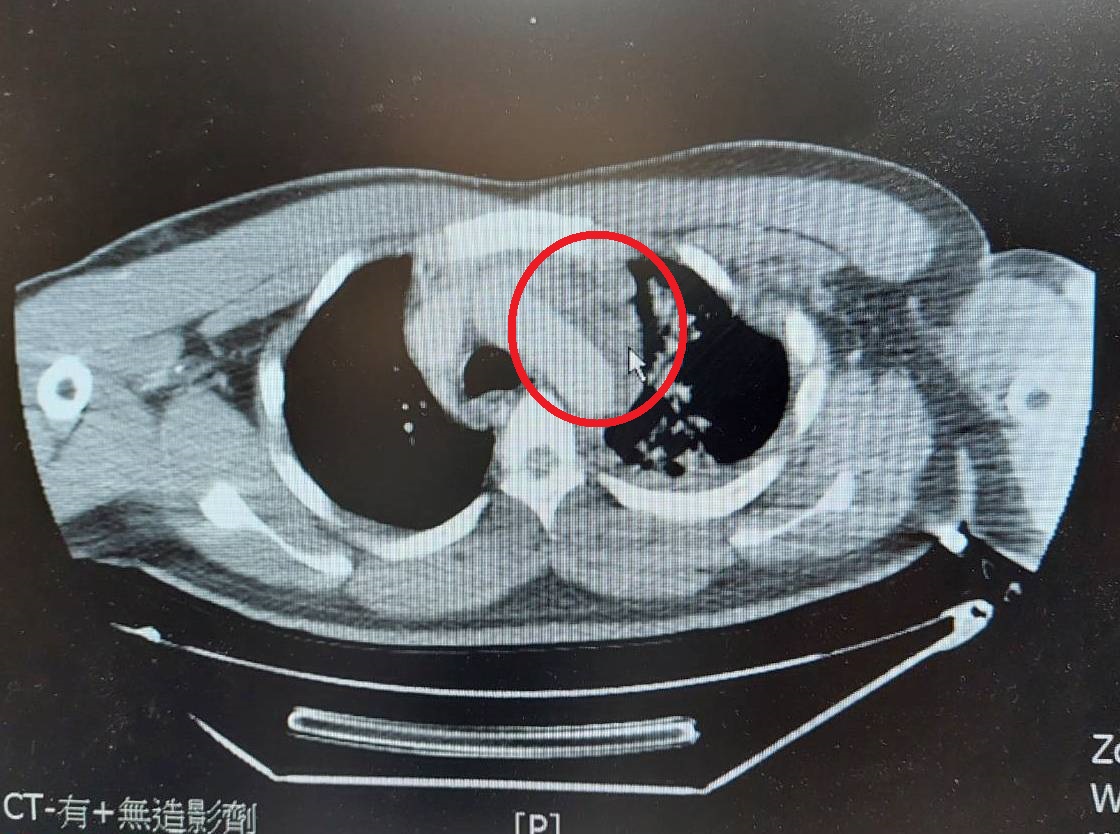

兩位傷者皆因車禍,發生嚴重外傷性興主動脈剝離(紅圈箭頭處),緊急接受手術穩定病情。

兩起車禍案例分別為20歲男性騎重型機車發生車禍,造成外傷性胸主動脈剝離合併縱膈腔出血、蜘蛛網膜下腔出血、頸椎及肋骨骨折;另一案例為25歲男性開車自撞,同樣有外傷性胸主動脈剝離合併縱膈腔出血問題,以及氣胸、血胸、肝臟撕裂傷合併出血、與左小腿骨折的狀況。由心臟外科執行微創主動脈血管支架置放手術穩定病情後,再由多科跨團隊合作治療與照顧,讓兩位傷者都順利出院。